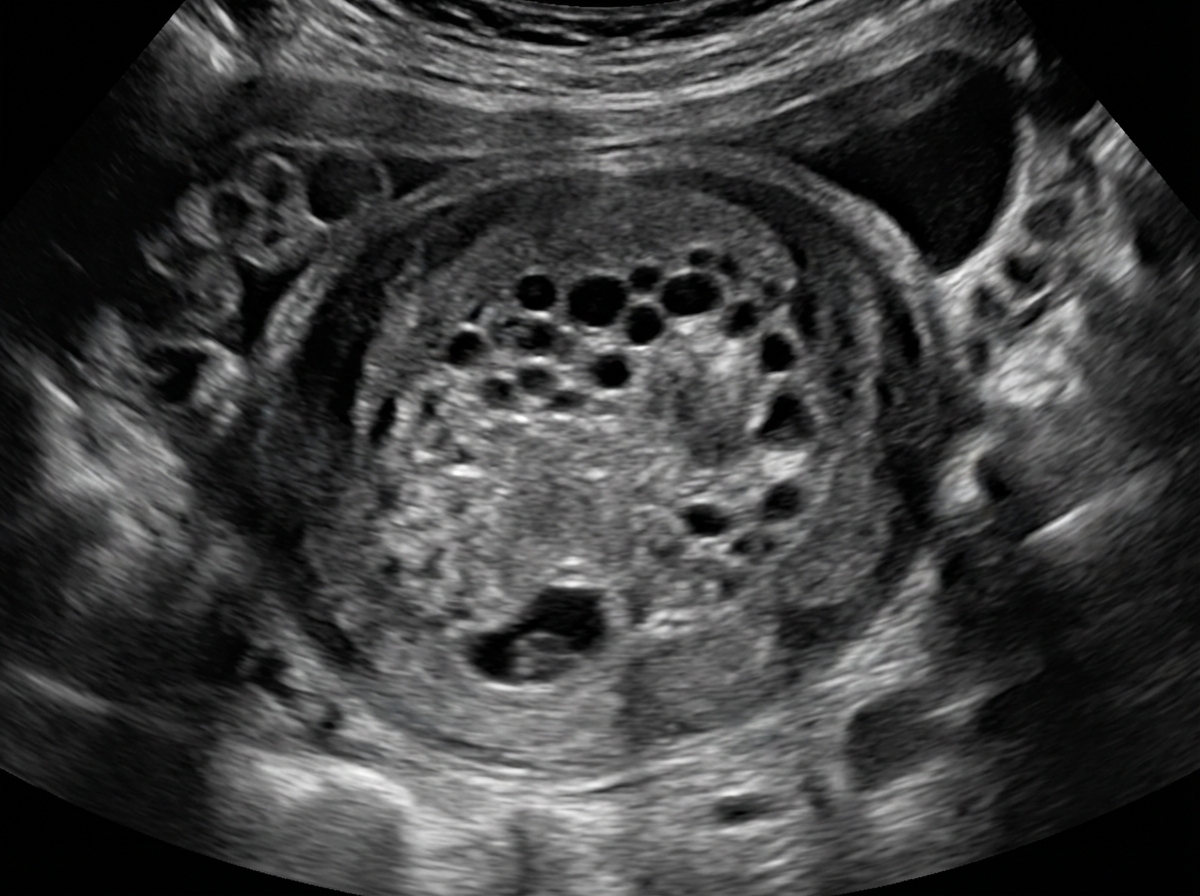

A 38-year-old woman presents to the emergency department with painless vaginal bleeding of sudden onset approx. 1 hour ago. The woman informs the doctor that, currently, she is in the 13th week of pregnancy. She also mentions that she was diagnosed with hyperemesis gravidarum during the 6th week of pregnancy. On physical examination, her temperature is 37.2°C (99.0°F), pulse rate is 110/min, blood pressure is 108/76 mm Hg, and respiratory rate is 20/min. A general examination reveals pallor. Examination of the abdomen suggests that the enlargement of the uterus is greater than expected at 13 weeks of gestation. An ultrasonogram shows the absence of a fetus and the presence of an intrauterine mass with multiple cystic spaces that resembles a bunch of grapes. The patient is admitted to the hospital and her uterine contents are surgically removed. The atypical tissue is sent for genetic analysis, which of the following karyotypes is most likely to be found?